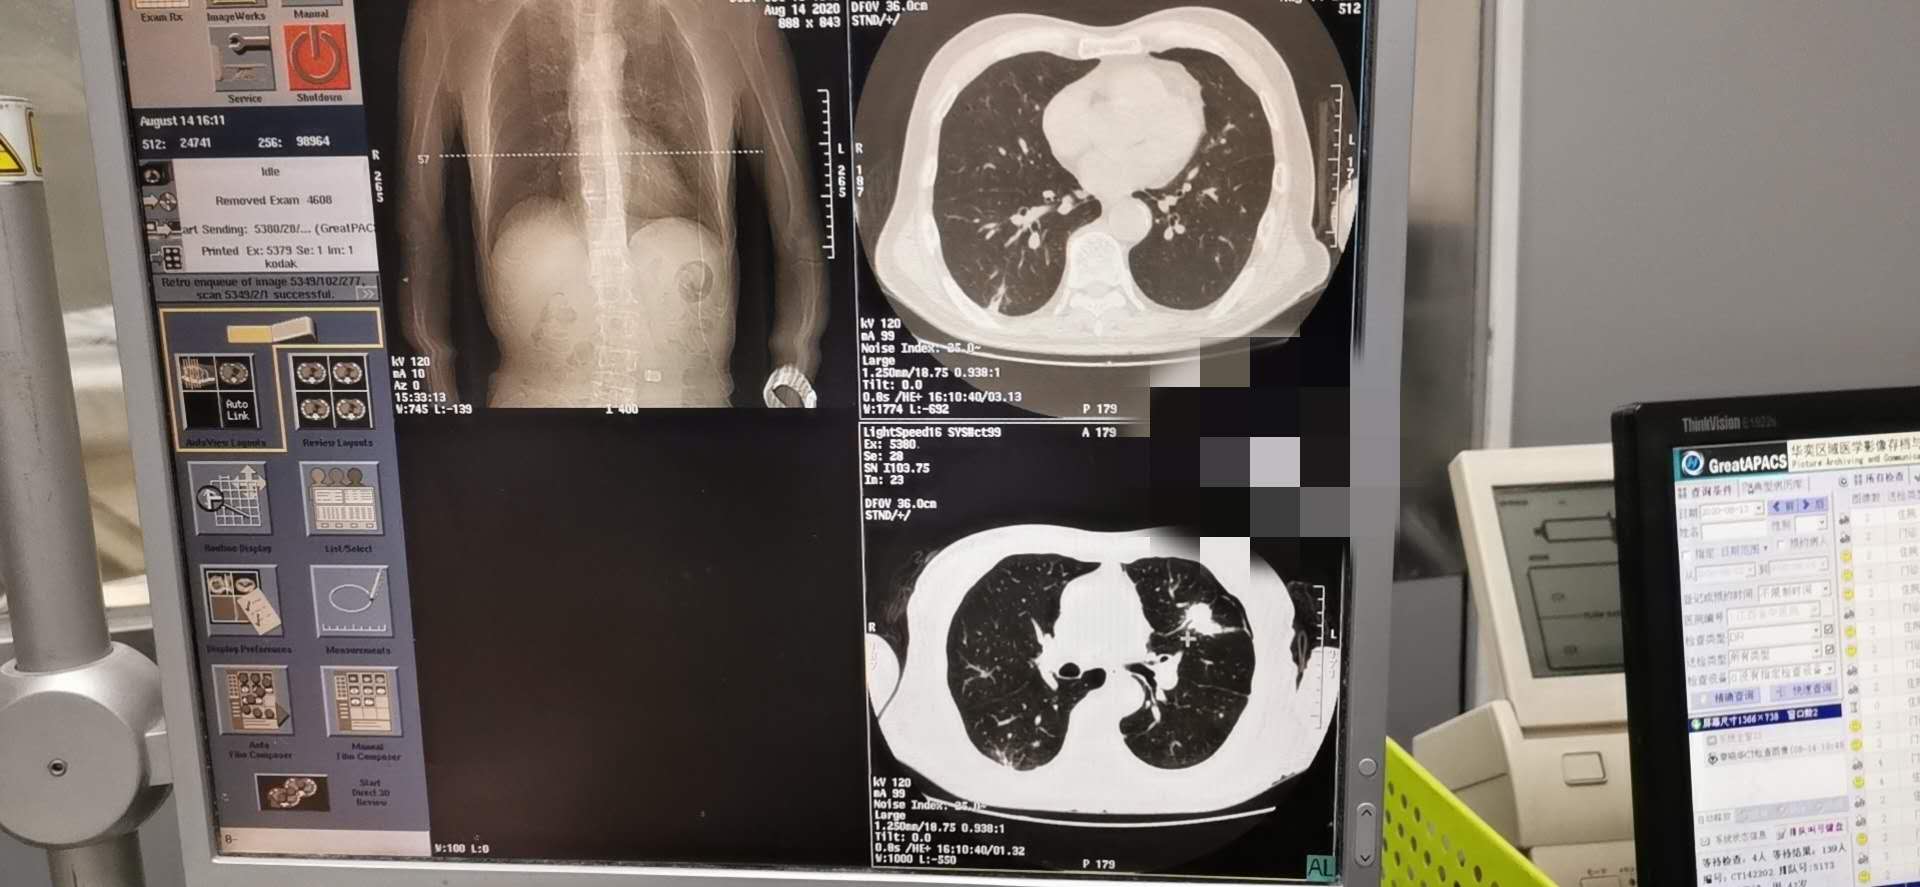

肺癌的发病率及死亡率高居恶性肿瘤之首,早诊断及早治疗尤为关键。 CT引导经皮穿刺肺活检诊断肺部疾患CT引导下穿刺适用范围广,临床应用最多。CT横断层扫描有良好的空间分辨率和密度分辨率,可准确显示病灶的大小、位置及内部情况,以及与血管等周围结构的解剖关系,尤其适用于定位难度大、病灶在肺门及纵隔附近者。当肿块与肺不张、阻塞性肺炎混合后,有时需行增强扫描才能确定肿块的实际大小。方法是指先作CT扫描确定病灶最佳的穿刺点,进针深度和角度,而后进行穿刺活检。常规CT下不能直接观察进针状况,必须在确定进针点后估算进针深度及进针方向,进针后再次扫描确认后方可行穿刺活检。CT引导下穿刺精确度高,对于0.5~1cm的病灶也可在CT导引下成功活检。因此对常规方法未能确诊的肺部结节病变、空洞病变、双肺弥漫性病变及纵隔肺门占位病变,应用CT引导下肺穿刺抽吸和切割针活检能取得较满意结果。尤其直径≤2cm肺部结节活检的准确性较高而并发症较低,可作为肺内孤立性小结节灶定性诊断的首选方法,其操作简单、安全、可靠。

为明确诊断及指导下一步治疗方案。我科洪禹霖副主任医师、张峰浩医师、吁佳副主任护师精诚配合下于8.14日成功完成一例肺小结节穿刺术,术后无明显气胸及出血并发症、患者安返病房。